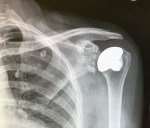

- My X-Ray after Replacement